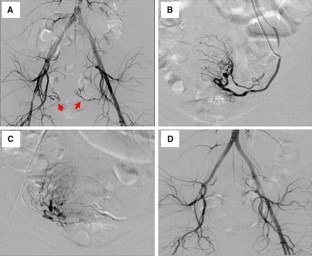

Fig. 1